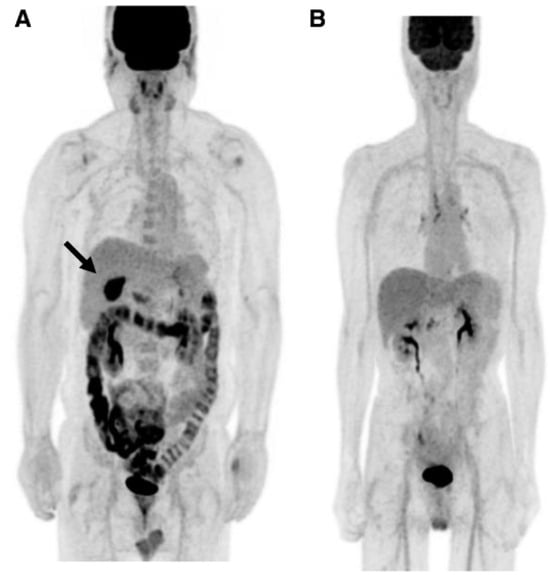

Morita and coworkers [171], by using positron emission tomography (PET)-MRI, recently found that the maximum standardized uptake value (SUVmax) of F18-FDG in the intestine (jejunum, ileum, and right or left hemicolon) of metformin-treated diabetics was higher than that of the control group. More importantly, the study permitted to differentiate the SUVmax of the intestinal wall from that of the intestinal lumen. The SUVmax of the intraluminal space in metformin-treated diabetics was greater than that of the controls (Figure 2). On the contrary, the SUVmax of the intestinal wall was similar in both groups [171]. A temporarily increased accumulation of the injected tracer seems to be observed (Figure 3) also in the liver of metformin-treated diabetics up to 48 h after interruption of the oral uptake of the drug [171,172,173], suggesting a persisting uptake of the radioactive glucose mediated by circulating insulin as consequence of the “metabolic starvation”(?) induced by the biguanide.

Figure 2.

PET-images taken 60 min after intravenous administration of F18-FDG in a diabetic patient treated with metformin (A) and in a control patient (B). In (A), radioactivity has accumulated in the last portion of the ileum and in the colon (right hemicolon, stronger than left hemicolon). The indication for the study was that gall bladder cancer was confirmed by the accumulation of the tracer in the gallbladder (arrow). From Morita Y et al. [171].